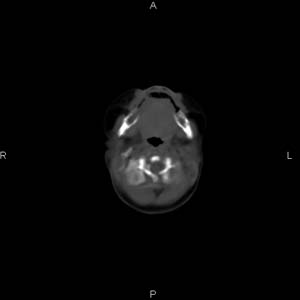

患者男,27天,出生后正常,今天中午在母亲怀里抱着吃奶在放下睡觉时发现后枕部慢慢出现一包块,来查头颅ct。无外伤史。包块内ct值47-51hu。请大家讨论。

支持脑膜脑膨出,双侧侧脑室三角区周围脑白质对称性低密度影,考虑缺血缺氧性脑病或肾上腺性脑白质营养不良。

\"中午在母亲怀里抱着吃奶在放下睡觉时发现后枕部慢慢出现一包块,包块内ct值47-51hu。

颅骨无缺损,骨缝无增宽.支持头皮血肿(血管破裂)